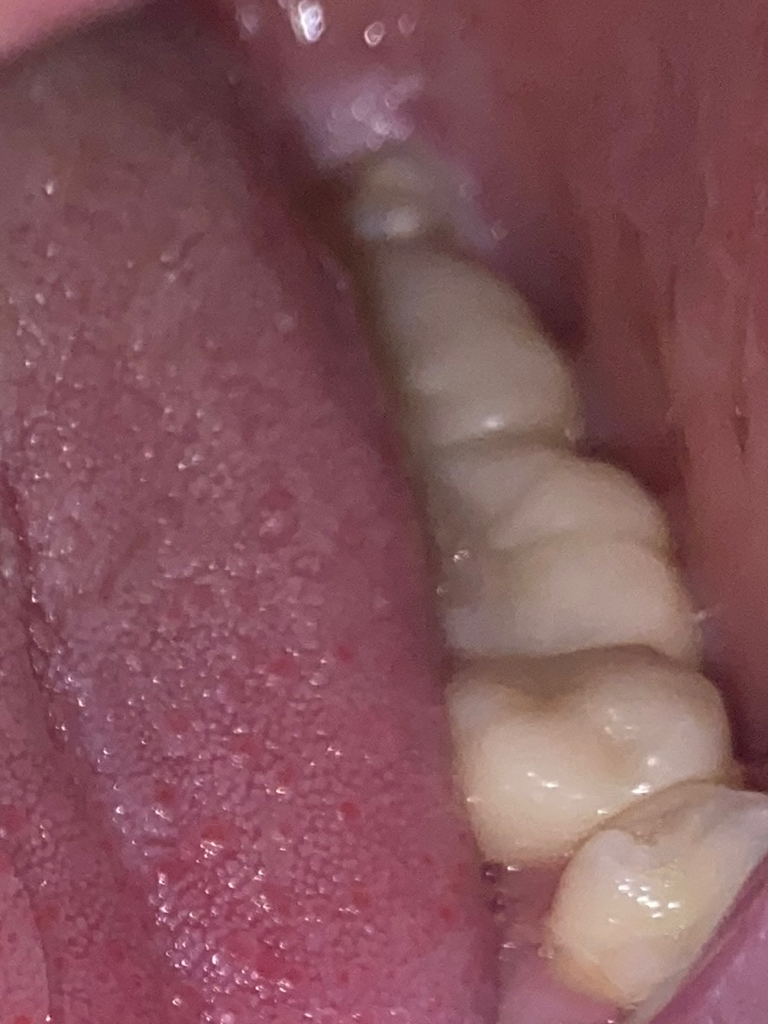

저 검은색으로 떼운 부분 (검색해보니 아말감?이라고하네요) 저 치아만 치아자체가 약간 검푸르게? 변했는데 저거때문인건가요 ㅠㅠ?? 한지 3-4년정도 됐어요 저 부분은 통증은 하나도 없어서 충치는 아닌거 같은데 ㅠㅠ

그리고 이 사진이 왼쪽 치료한건데 어금니 2개 +기존 아말감으로 했던거 1개 교체까지 개당 50 / 3개 150들었던거 같은데 뭘로 치료한건지 알 수 있을까여,, 여기 치료한건 하나도 통증없구 티도 안나가지구 좋은데 방문시에 의사쌤들은 보시면 뭐로 한건지 알 수 있나요??